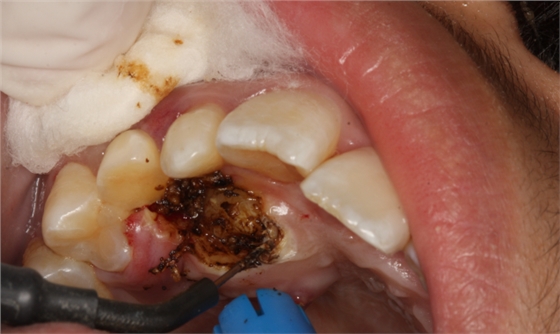

圖7.局部麻醉下、電刀切除覆蓋在13上的腭側(cè)粘膜組織。

圖8.繼續(xù)電刀切除腭側(cè)粘膜組織

圖9.清理切除部分腭側(cè)組織后的13牙冠。